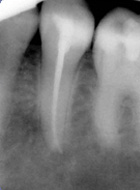

Ist der Zahnnerv durch Karies oder seltener, durch einen Unfall so geschädigt, dass er entfernt werden muss, wird eine Wurzelbehandlung notwendig. Dabei wird der Nerv entfernt, der Zahn bzw. die Zahnwurzel gereinigt und desinfiziert und danach mit einem oder mehreren Kunstharzstiften gefüllt. Er bekommt eine Wurzelfüllung.

Wird diese Behandlung mit der notwendigen Sorgfalt durchgeführt, kann der Zahn danach, wie jeder gesunde Zahn, weiter seine Arbeit verrichten. Allerdings wird häufig nach einer Wurzelbehandlung, zum Schutz des Zahnes, eine adhäsive Kunststoffversorgung oder seltener eine Überkronung notwendig.